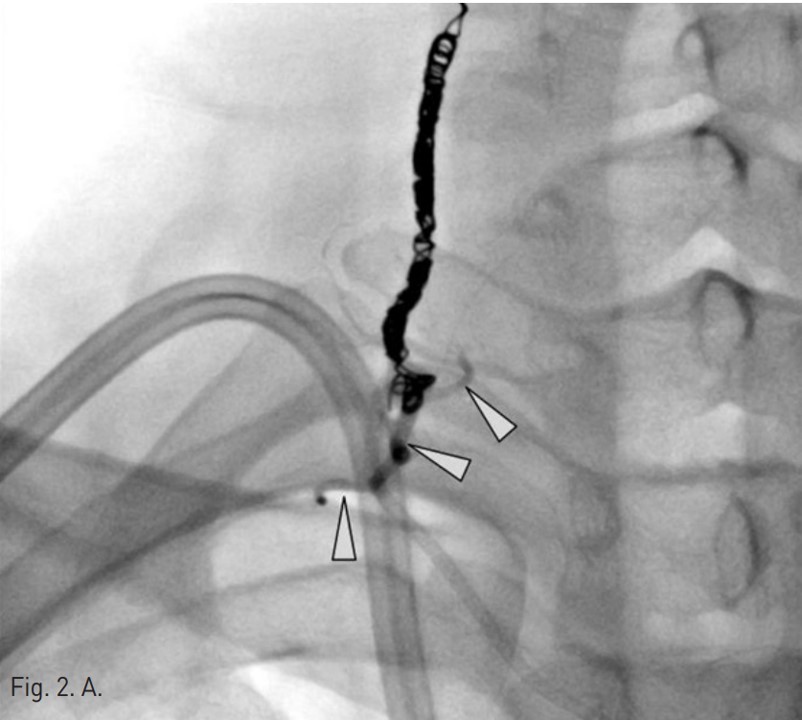

Permanent catheter insertion 이후 일주일 뒤 시행한 혈관조영술에서 갑상목동맥(right thyrocervical trunk)의 branch에 작은 거짓동맥류(small pseudoaneurysm)가 있고 permanent catheter를 insertion하는 과정에서 비롯된 합병증으로 판단되었음(Fig. 1A,B). 따라서 갑상목동맥의 기시부에서부터 아래 갑상동맥(inferior thyroidal artery)의 기시부까지 색전술을 시행하기로 함. Microcoil 및 glue를 사용하여 embolization 시행 후 조영제 검사에서 거짓동맥류는 보이지 않고(Fig. 2A,B) 임상 소견도 모두 호전되었음.

아래갑상동맥의 원위부의 색전을 방지하기 위해서 한 개의 coil(F-IDC 2D 3x6cm, Boston scientific)이 사용되었고 아래갑상동맥의 기시부에 색전술을 시행하였음. 그 후에 아홉 개의 microcoil(Tornado microcoil, Cook)과 one vial의 glue(Histoacryl 0.5cc)를 이용하여 아래갑상동맥과 갑상목동맥에 색전술을 시행함.

색전술 후 혈관조영에서 오른쪽 갑상목동맥은 성공적으로 색전이 되었고 더 이상 거짓동맥류는 보이지 않았음(Fig. 2A,B).

Fig. 2. A

Fig. 2. On post-embolization angiography, the right thyrocervical trunk was successfully embolized and the pseudoaneurysm was not visualized. The embolization was done using nine of microcoils and one vial of glue(arrow head).